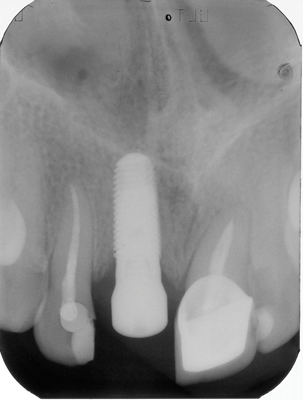

Fig 5. A 35-year-old patient with a missing central incisor due to trauma was restored with an implant (Fig 5, day of second-stage surgery). Twelve years later she presented to the office complaining that pus was draining from the implant and she felt uncomfortable. As can be seen in Fig 6, severe peri-implant bone loss due to peri-implantitis was evident.

Figure 5

Fig 6. A 35-year-old patient with a missing central incisor due to trauma was restored with an implant (Fig 5, day of second-stage surgery). Twelve years later she presented to the office complaining that pus was draining from the implant and she felt uncomfortable. As can be seen in Fig 6, severe peri-implant bone loss due to peri-implantitis was evident.

Figure 6

Peri-implantitis is an inflammatory disease affecting the tissues around dental implants. It is characterized by inflammation in the peri-implant mucosa and progressive loss of the implant-supporting bone (Figure 5 and Figure 6).36 A meta-analysis estimated the prevalence of peri-implantitis to be 22%, and it increases as a function of time.37 A recent study indicated that implants in the maxillary anterior and mandibular anterior regions had a higher prevalence of peri-implantitis than the maxillary posterior region,38 making the esthetic zone a risk area for the long-term success of dental implants.

The clinical appearance of peri-implantitis defects may vary and is dependent on the nature of the implant's surrounding hard and soft tissues (eg, thin or thick phenotype), severity of bone resorption, and level of inflammation. In the absence of treatment, peri-implantitis progresses in a nonlinear and accelerating pattern.36